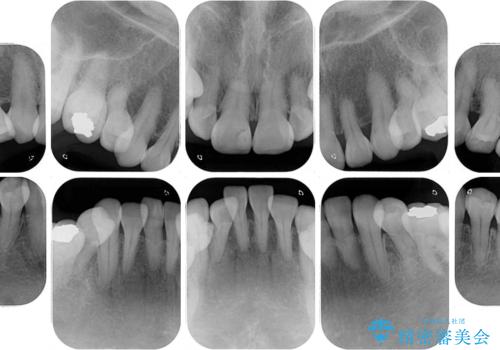

- 小さいころからの歯の変色と矯正治療の後戻りを気にして来院された患者様です。

気になる変色歯を仮歯に変え、その後歯列不正を矯正治療で改善し、最後にオールセラミッククラウンにて補綴治療することとしました。